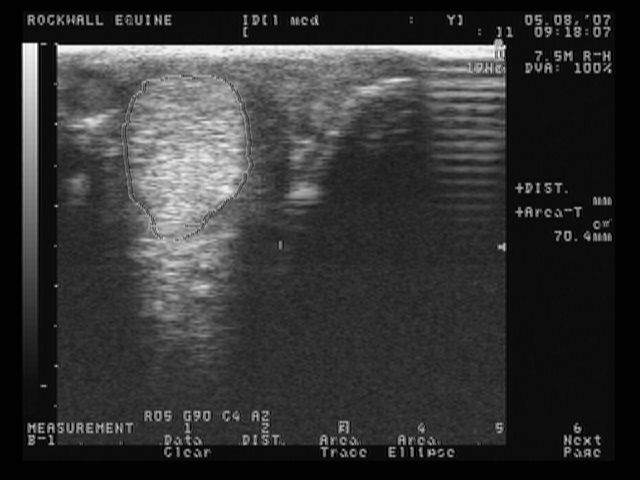

left medial front

These are the most recent ultrasound images of my horses legs, done about 2 weeks ago. The original injury was in January, so he is about 4 months into healing. The left lateral is normal.